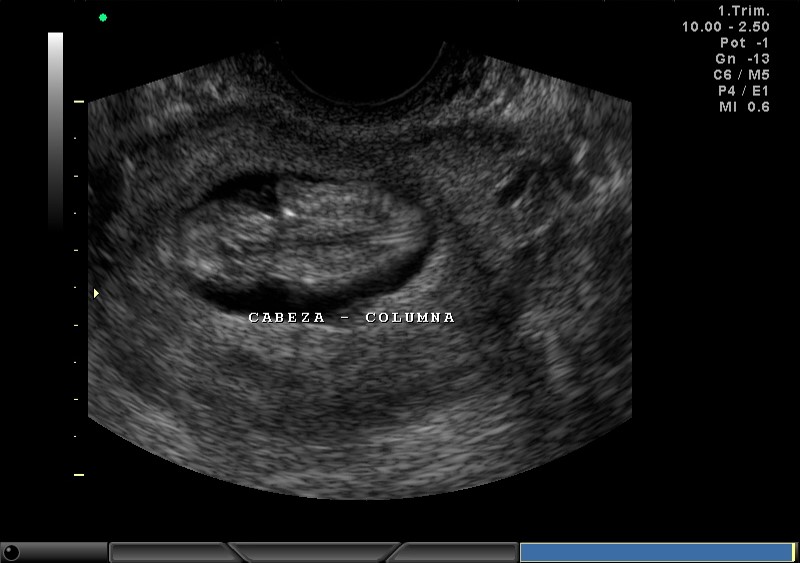

2D, CABEZA, COLUMNA, COSTILLAS